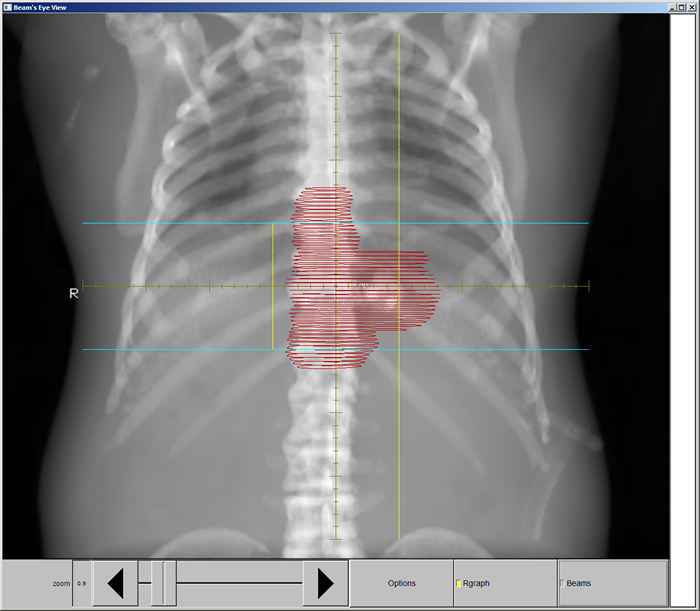

This case will be an abdominal tumor. Because of previous Radiation, the MD has given us OAR limitations that will require IMRT Treatment planning.

Plan Directives; Dose: 50 GY (2Gy X 25fx)

95% of PTV Receives 100% of Rx

Nothing receives > 110% of Rx dose (if possible)

Spinal Cord: .1cc < 25GY

Rt Kidney: Mean Dose < 18 Gy

Lt Kidney: Mean Dose < 18 Gy

Lungs: V5 < 50%

V20 < 15%